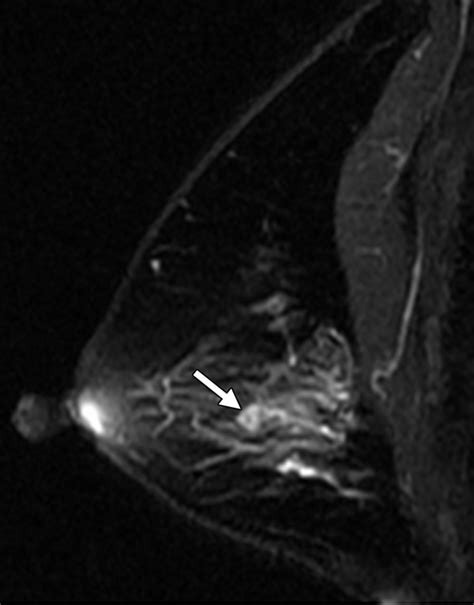

Breast Ultrasound High-resolution imaging used to evaluate lumps and look inside the ducts for abnormal growth.

Ductogram (Galactogram) A specialized test where contrast dye is injected into the affected duct to visualize the blockage or growth.